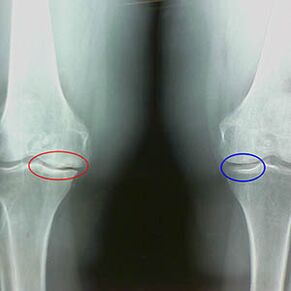

Determine the degree of arthritis occurring by x -rayRevealing participation in the pathological process of bone structure.Their change indicates that the muscular system has been imbalance for 5-10 years.As a rule, everyoneFor many years, they experienced pain.

At the first stage of arthritis, was discovered by accident, the slight increase of the bone nose occurred.The growth appears in places with the greatest instability of the joint.Typically, patients rarely suffer from pain or discomfort during the move.

The second stage of muscle disease is considered easy.X -ray shows significant spearheads, but cartilage is not affected.The amount of fluid fluid decreases, but the pain symptoms appear after walking and running long, the stiffness in the joints and aches and pains when bent and at the knee position.

Early X -Ray features of the second phase of knee disease:

- The pointed edges of the Inter -Recrip tube on the tibia, where the cross -shaped ligament is attached;

- narrowing the general gap on the intermediary;

- The pointed edges of the bone types on both sides of the intermediary, less often on the side - depending on the development of Valgus or variant joint deformation.

For the second phase in LarsenThe narrowing of the general gap of more than 50% is characteristic, but this can only be tested in dynamics or comparison with an unlike joint.

Signs of moderate arthritis of the knee joint in the third stage:

- The joint distance is significantly narrowed;

- The presence of scleroderma under the doses in the loaded parts;

- Countless bones on the edges;

- A rare appearance of the follicles under the epidural;

- Synovites, the appearance of a capsule of a baker under the knee;

- The surface is uneven thighs and tibia, loss of joints;

- Change the shape of the tea cake bone;

- Focus of calcification and chondromation;

X -ray shows the presence of bone cells, a change in the space between the femur and tibia, showing the loss of cartilage in the knee.Sometimes the X -Ray of the knee joint shows significant signs of cartilage wear, but the patient is not significantly painful.On the contrary, early stage arthritis can break the function of the knee, because the cause of pain is tropical muscle.